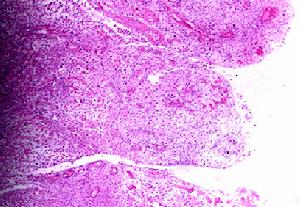

腎癌細胞具有多能性,其組織和細胞相多樣典型的是透明細胞,故又稱透明細胞癌,亦有為顆粒細胞癌,或混合型。還有梭形細胞癌,預後不良。